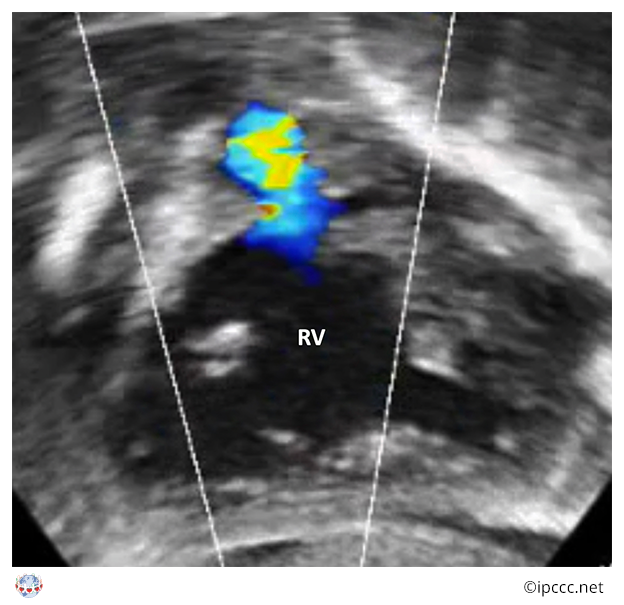

A group of congenital cardiac malformations with biventricular atrioventricular alignments or connections characterized by anterosuperior deviation of the conal or outlet septum or its fibrous remnant, narrowing or atresia of the pulmonary outflow, a ventricular septal defect of the malalignment type, and biventricular origin of the aorta. Tetralogy of Fallot will always have a ventricular septal defect, narrowing or atresia of the pulmonary outflow, aortic override, and most often right ventricular hypertrophy.

Echocardiogram